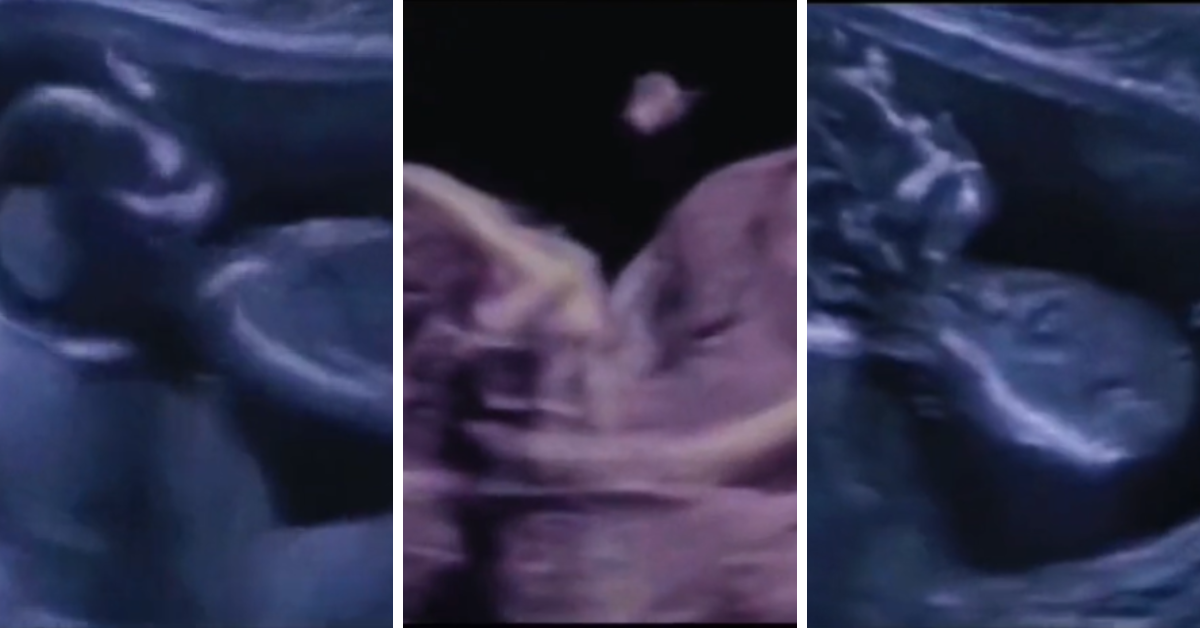

Štucanje prati isti, ritmični pokret kao disanje, ali snažnije. Celo telo fetusa se kreće u trzajućoj kretnji sa svakim štucanjem, što mnoge trudnice mogu da osete. Kao i kod beba i odraslih, štucanje fetusa se javlja u kratkom, doslednom vremenskom periodu, a zatim nestaje samo od sebe.

Pogledajte video: